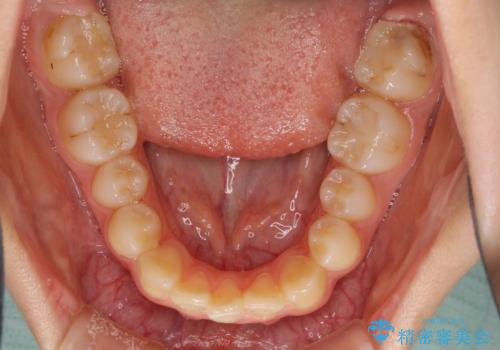

- 目立つ八重歯を改善したいとのことで来院された患者様です。

奥歯の咬み合わせは左右とも理想的なものでしたが、下顎前歯が1本欠損しているため、上下のバランスを保つことが難しい歯列でした。

まずは補助装置を用いて八重歯を改善し、インビザラインにて歯列を整えましたが、当初の懸念が的中し、臼歯部の咬合を安定させることができませんでした。

海外留学の予定もあったため、後半は上下ワイヤー装置にて矯正治療を継続し、違和感なく咬合させることとなりました。